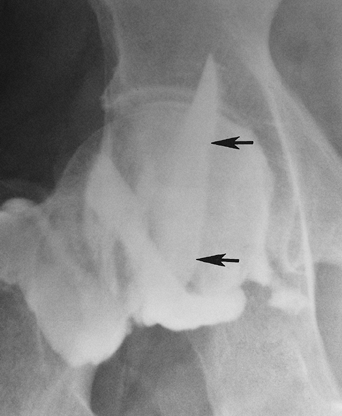

![]() |

FIGURE 4-24 Hip arthrogram/injection with filling of the iliopsoas bursa (arrows).

P.162

FIGURE 4-25 Coronal fast spin-echo T2-weighted image demonstrating an enlarged iliopsoas bursa (arrows) with low signal intensity filling defects because of chronic synovitis.